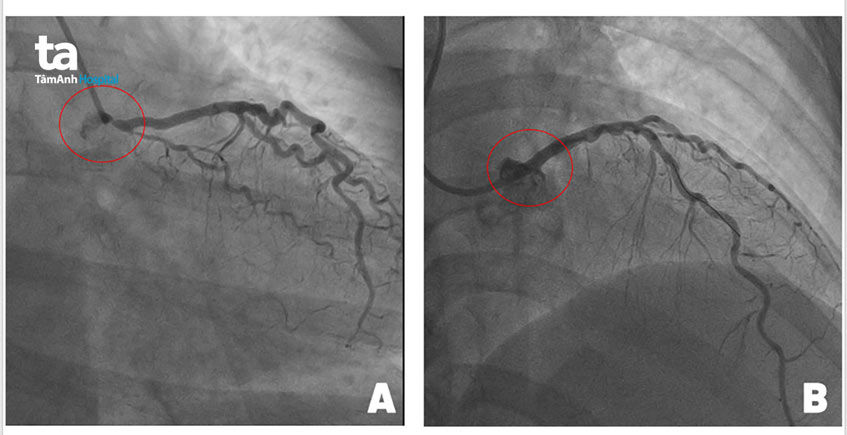

Bà Nguyễn Hồng Nga (55 tuổi, ngụ Q.1, TP.HCM) xuất hiện triệu chứng hụt hơi, khó thở, nghẹn ở cổ khi đi bộ chừng 100m. Thăm khám tại Bệnh viện Đa khoa Tâm Anh TP.HCM, bác sĩ cho biết bệnh nhân có dấu hiệu của nhiều bệnh lý như hô hấp, trào ngược dạ dày – thực quản, suy tim, bệnh mạch vành. Sau khi loại trừ các bệnh lý liên quan, bác sĩ tiến hành khảo sát bệnh tim mạch. Kết quả đo điện tim, siêu âm tim lúc nghỉ hoàn toàn bình thường, nên khi kiểm tra chuyên sâu hơn bằng siêu âm tim gắng sức có thuốc phát hiện tim bà gần như ngừng đập dù chỉ gắng sức nhẹ. Kết quả chụp mạch vành (DSA) cho thấy bệnh nhân bị hẹp khít lỗ xuất phát thân chung động mạch vành trái (mạch máu chính nuôi tim) khiến tim bị thiếu máu nghiêm trọng. Nguy cơ đột tử rất cao!

Khi tiến hành nong mạch đặt stent cho bà Nga, bác sĩ đưa ống thông qua đường động mạch quay tiếp cận mạch máu bị tắc. Do vị trí hẹp nghẽn tại thượng nguồn mạch máu khiến trái tim có thể ngưng đập khi thao tác thủ thuật, nên êkip phải phối hợp ăn ý, dứt khoát, nhanh chóng, không gây cản trở dòng máu đến tim. Các bác sĩ vừa nong mạch vừa kết hợp siêu âm lòng mạch (IVUS) để “canh” vị trí đặt stent chính xác: không quá ngắn (để phủ hết sang thương) cũng không quá dài (nhô vào động mạch chủ quá nhiều sẽ khiến các thao tác sau đó trở nên khó khăn).

Tuy là thủ thuật ít xâm lấn nhưng cũng tiềm ẩn rủi ro bệnh nhân có thể ngưng tim trên bàn thủ thuật nên các bác sĩ đã dự phòng hệ thống tuần hoàn tim phổi ngoài cơ thể (ECMO) sẵn sàng ứng cứu. May mắn, mọi việc diễn ra thuận lợi và chỉ trong vòng 20 phút, êkip tái thông thành công dòng máu qua thân chung động mạch vành trái cho bệnh nhân. Khoảng thời gian thực hiện chỉ bằng 1/3 khoảng thời gian lý tưởng theo khuyến cáo của Hiệp hội Tim mạch châu Âu và Mỹ là 60 phút.